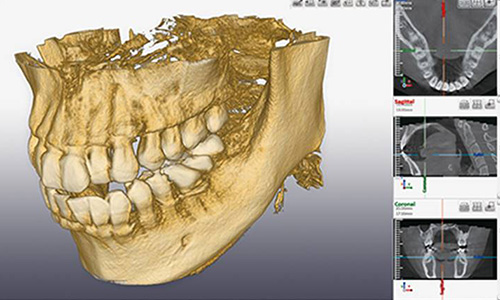

歯科用デジタルCT撮影

当院にて撮影可能です。一定の条件下で保険適応になります。

レントゲンと歯科用CTも内部組織を写し出すことに変わりありませんが、パノラマレントゲンと得られる画像の次元が異なる点が決定的な違いです。従来のレントゲンは、「二次元」、歯科用CTは「三次元」で撮影できます。

一方の歯科用CTは、立体的な画像が得られるので、病巣の位置だけでなくレントゲンでは判断が難しかった骨の厚みや骨密度がわかります。